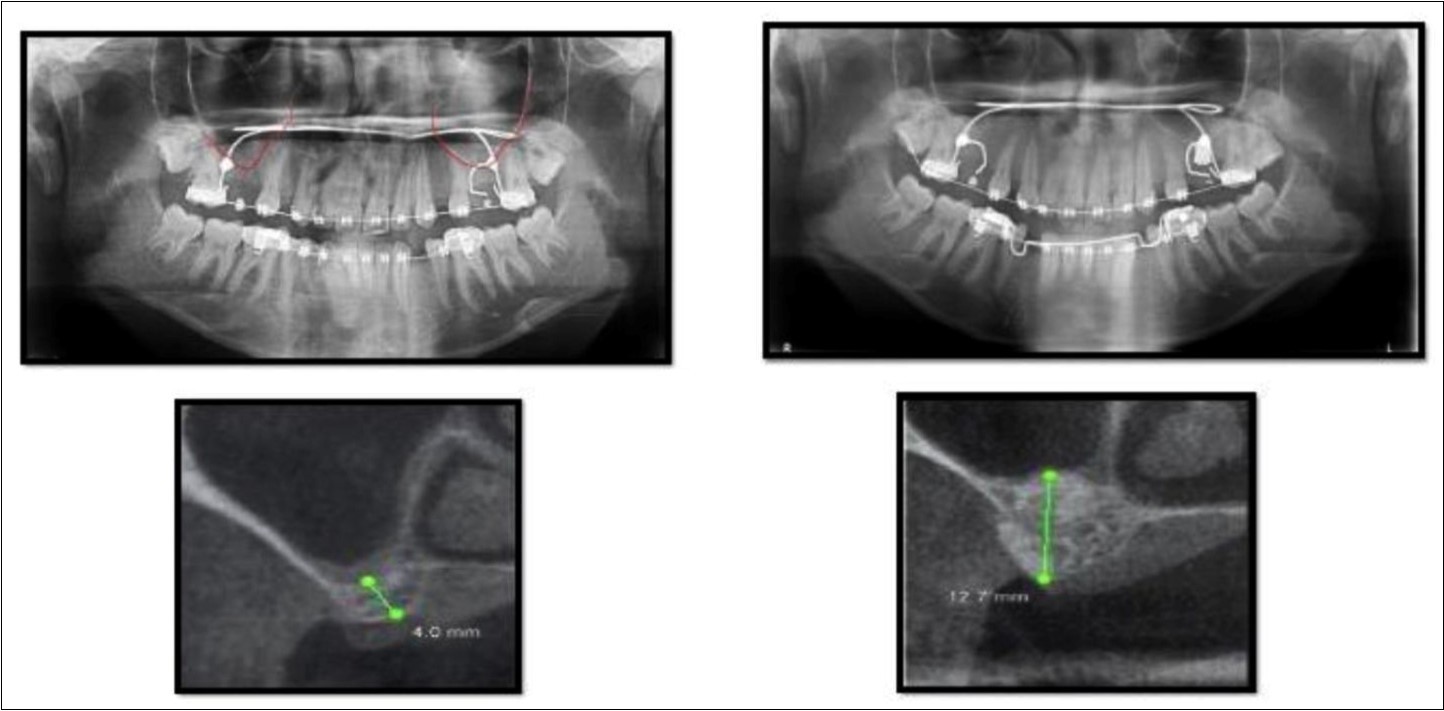

A 19 year old young woman was referred to Department seeking options for rehabilitation of missing right upper first molar with fixed prosthesis as she was uncomfortable with the removable partial denture in relation to 16. The residual bone height in region was 4 mm in 16 tooth region. Patient was taken-up for direct sinus elevation via lateral window approach for sinus augmentation in relation to 16. Under aseptic conditions and local anesthesia, lateral wall of maxilla was exposed after muco-periosteal flap elevation. A window was created of 1cm diameter corresponding to apical aspect of 16. Sinus membrane was identified and elevated using sinus elevators and reamers without perforating the lining. Once the sinus membrane was elevated, graft material was dispensed to achieve an augmentation of 1cm assessed clinically and confirmed using post-operative OPG. At the end of 6 months, a CBCT scan showed an increased bone height of 12.7 mm. (Figure 6)

Figure 6.Pre-operative and post-operative Orthopantomographs and cross sections of CBCT showing residual alveolar bone height